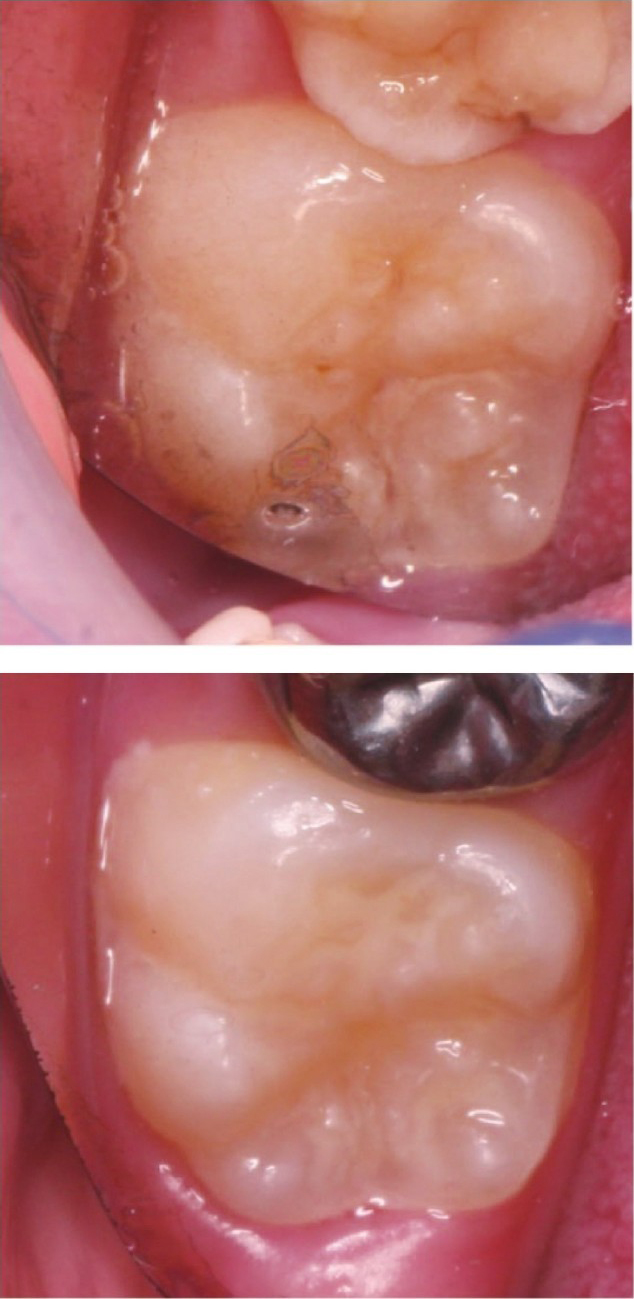

窝沟封闭(Pit and Fissure Sealant):应用某种材料于龋易感的咬合面点隙和窝沟,形成一个微机械粘接保护层,切断致龋菌的营养来源,达到防龋的效果。窝沟封闭是预防窝沟龋最有效的方法(图2-1)。

图2-1 窝沟封闭前(上)后(下) QxfBddHU3NFrt84rrvvpLGc6Oa3CD0hEgSy0CjJiEG2JosaMbaD82Jz5yeZHeWq6